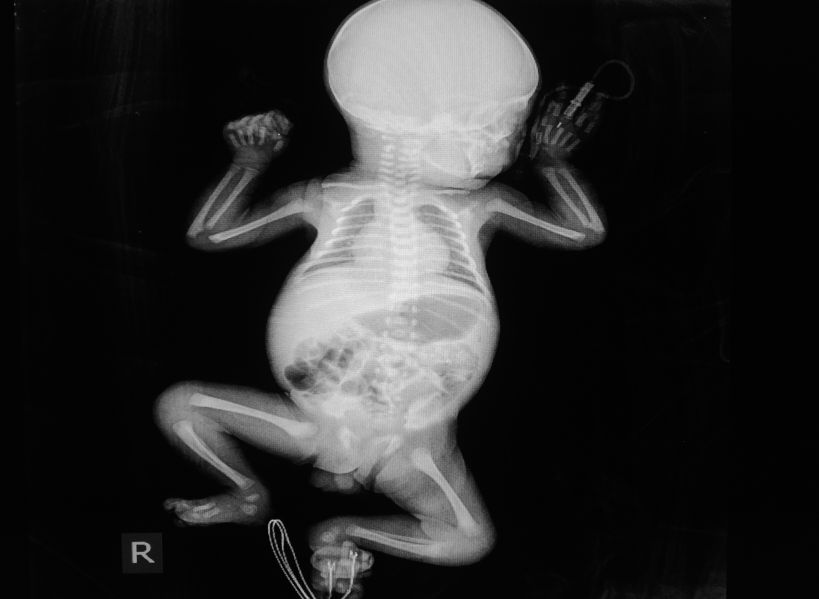

Fracturas durante el parto

Las fracturas infantiles a veces pueden ser el resultado de prácticas de parto natural. Sin embargo, en muchos casos, son causados por errores médicos durante un parto difícil. Algunos de los tipos más comunes de fracturas de huesos en recién nacidos incluyen:

• Fractura de clavícula: los bebés más grandes que el promedio son más susceptibles a sufrir una fractura de clavícula durante el parto. Cuando un bebé se atasca en el canal de parto, puede ocurrir una fractura de clavícula. Estas fracturas también pueden resultar del uso inadecuado o agresivo de herramientas de parto como fórceps o aspiradoras.

• Fractura de húmero: estas lesiones en el hueso largo de la parte superior del brazo pueden notarse por la falta de movimiento del brazo en un recién nacido. Un parto apresurado por los médicos puede provocar una fractura de húmero. Cuando el parto se apresura, la cabeza del bebé se puede empujar rápidamente a través del canal de parto, pero el cuello y los hombros se atascan. Cuando un parto ocurre demasiado rápido, pueden producirse fracturas de húmero.

• Fractura de fémur: las fracturas de fémur, o roturas en el fémur, son bastante raras en los recién nacidos y son sintomáticas de un parto inadecuado. A diferencia de otras fracturas, las de fémur durante el parto se han asociado con un nacimiento con peso bajo. Las cesáreas pueden reducir el riesgo de una fractura de fémur, pero pueden tener otros factores de riesgo.

• Fractura de cráneo deprimido: las lesiones por fractura de cráneo deprimido son raras y solo ocurren en aproximadamente 4 a 10 nacimientos por 10,000, según el Centro Nacional de Información Biotecnológica. Este tipo de lesión se ha relacionado en gran medida con el uso inadecuado de instrumentos en el proceso de parto y rara vez se observa en partos en los que no se utilizan instrumentos.